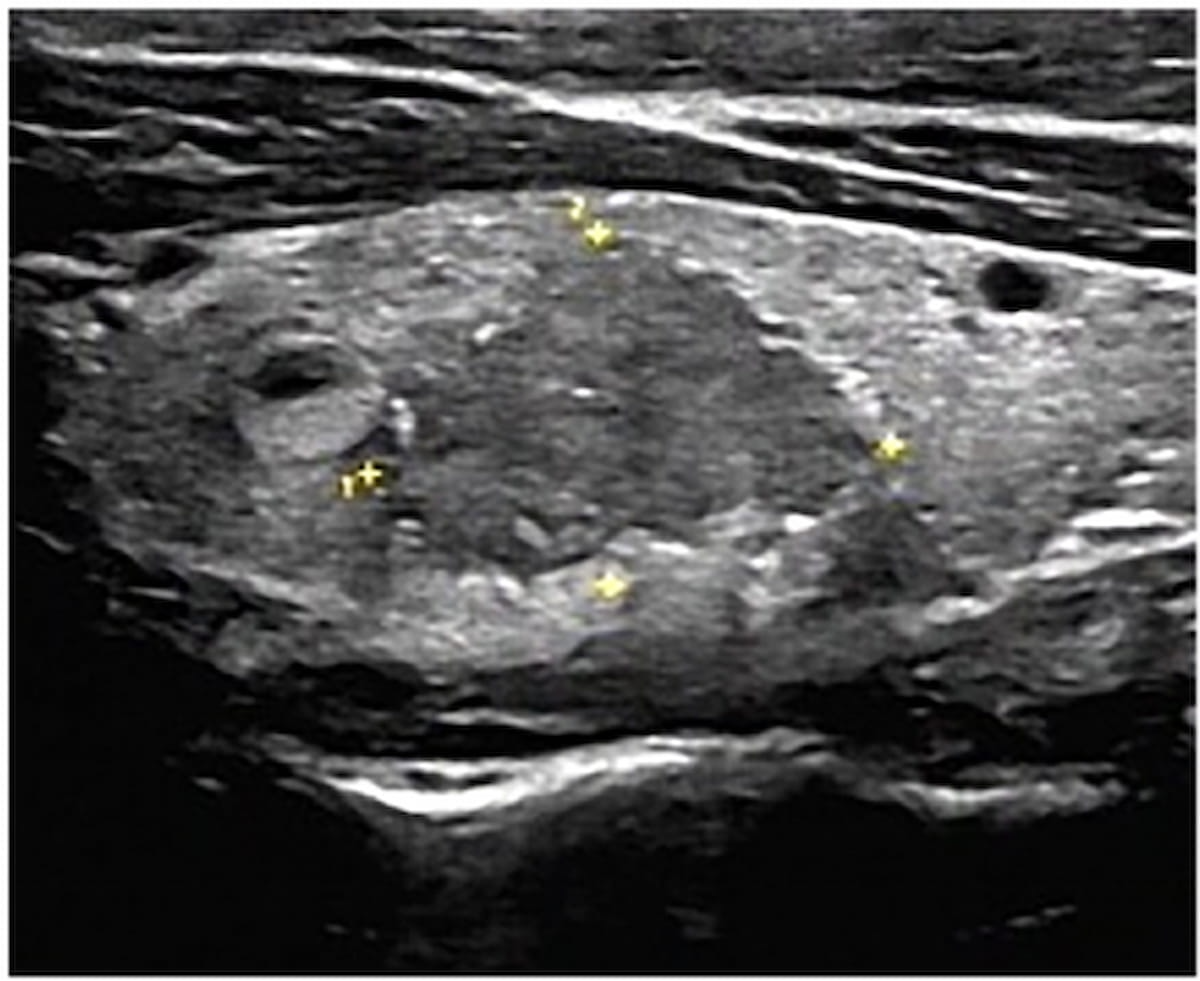

Here one can see an ultrasound image revealing a thyroid nodule with type III calcification. An emerging nomogram model provided an 88.2 percent AUC in differentiating between malignant and benign thyroid nodules in a recent study. (Images courtesy of Academic Radiology.)

The study authors found that the ultrasound-based nomogram offered an 88.2 percent AUC for predicting malignancy in thyroid nodules with peripheral calcification. Researchers also noted a sensitivity of 90.9 percent, a specificity of 73.7 percent and a negative predictive value of 89.4 percent for the nomogram.